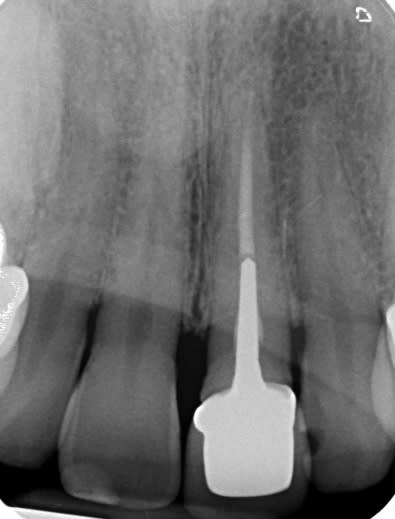

Ah ben c'était une richmond, du coup...

J'ai trois cas en tête:

-un petit papi à qui j'avais tout refait, avec la ferme intention qu'il emmène le boulot dans sa tombe. J'avais laissé UN putain d'IC qui paraissait nickel à tout point de vue, sur la 13 support de bridge. Fracture radiculaire 3 ans plus tard.

-une jeune présentant une ccm en surcontour, sur un ic en surcontour, sur 35 de mémoire; vu les vibrations engendrées par la reprép de l'IC, décision de déposer pour éviter un descellement plus tard: une heure de boulot, un paquet de transmétal, et un max de fatigue mécanique pour la racine résiduelle.

-une autre jeune, ccm en surcontour, sur un ic en surcontour, à nouveau, une 25. Cette fois, pas con, je reprep l'IC, l'endo est clean à la radio, empreinte. Le jour de la pose, l'IC vient avec la pro, et le canal palatin n'est pas traité.

Je n'ai pas encore formulé mes conclusions.